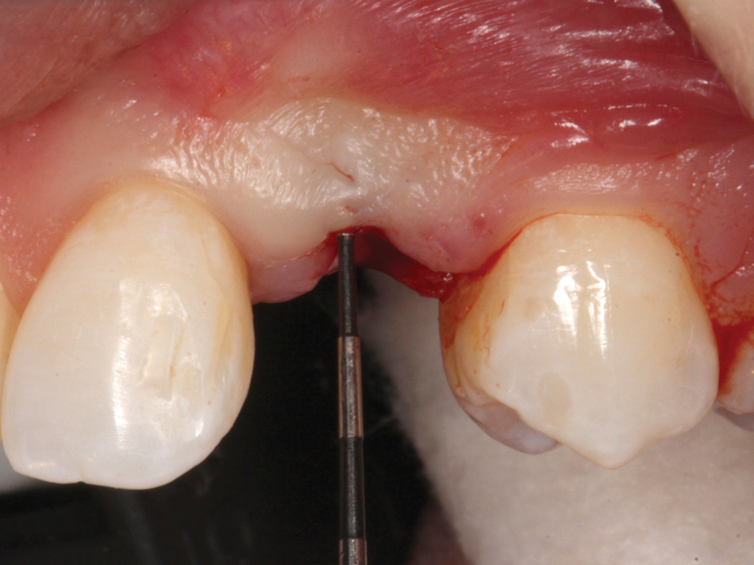

(47.) The primary stability of the implant was confirmed to be sufficient for immediate loading.

Figure 47